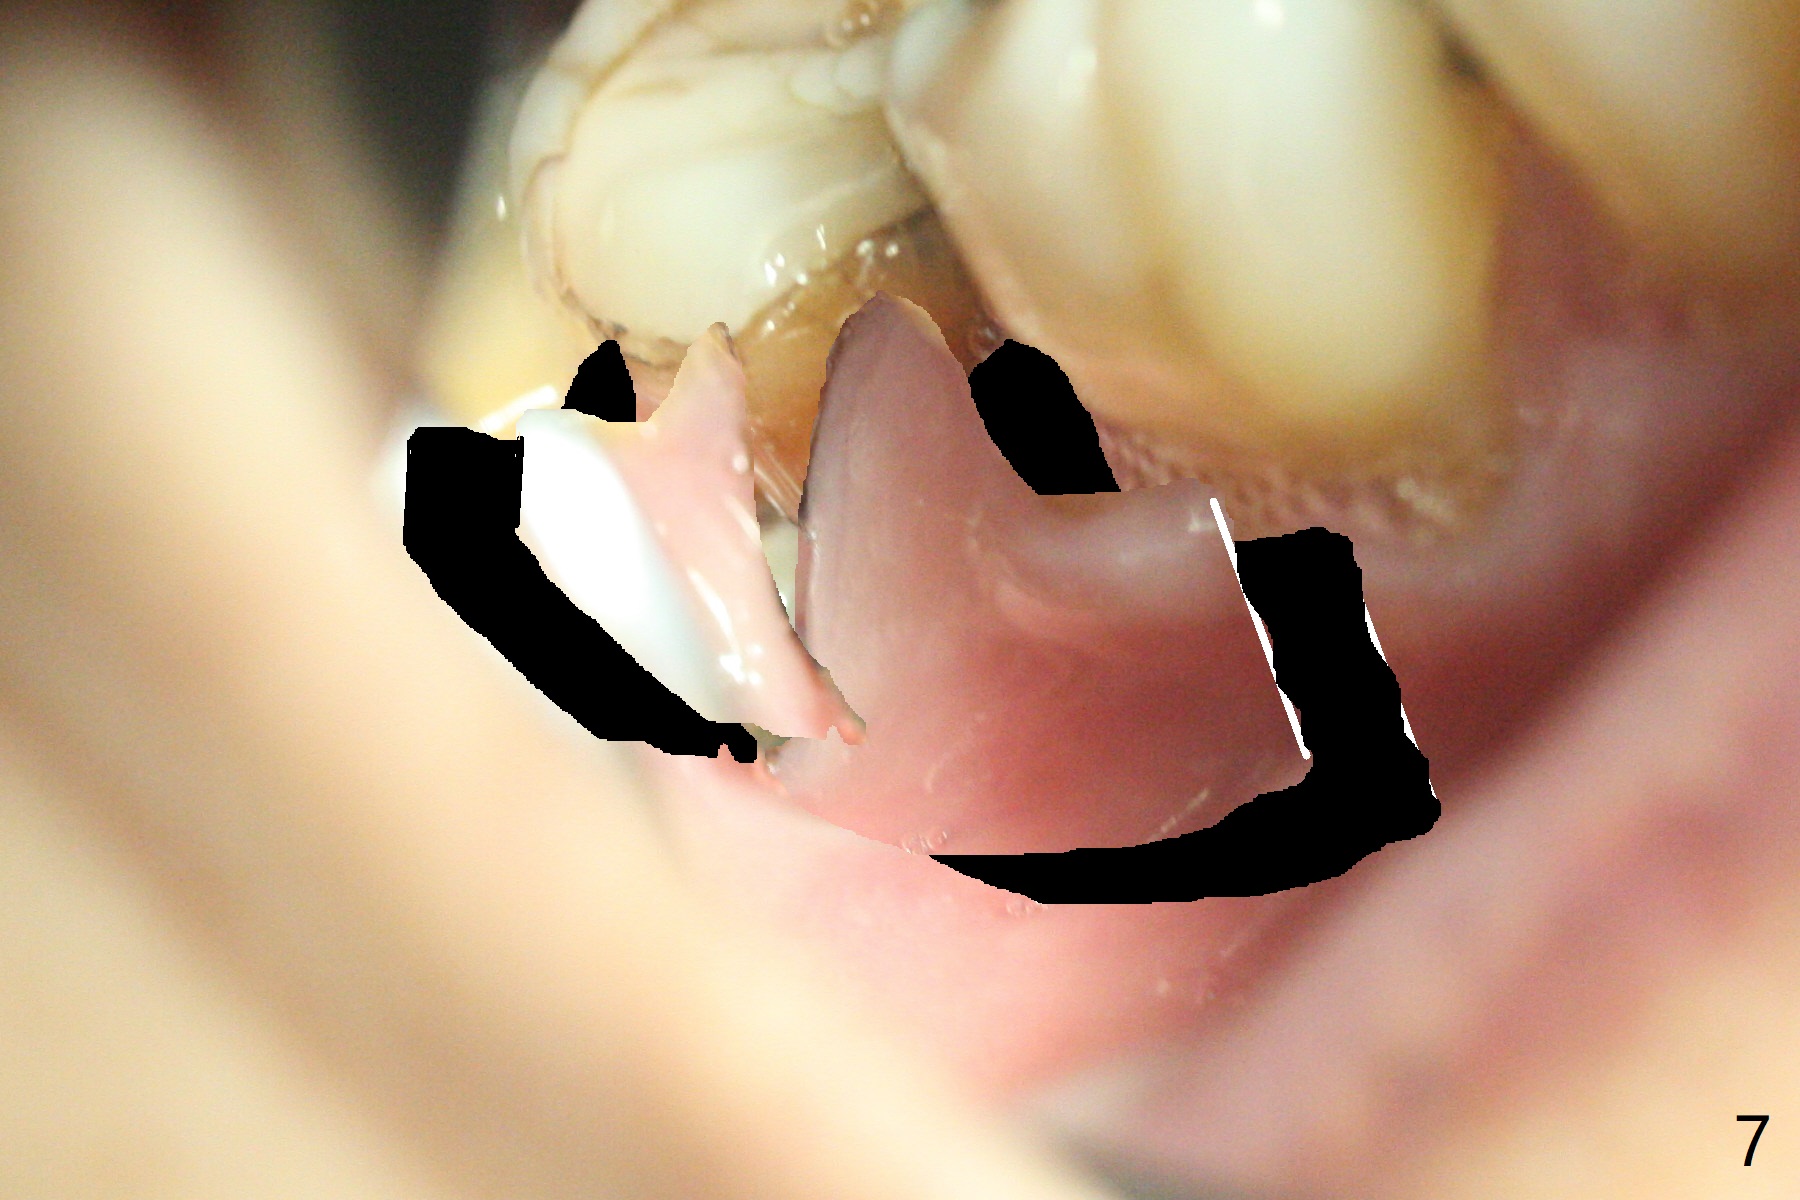

In fact the buccal gingival recession at #31 is asso-ciated with cervical caries perfor-ation (Fig.1 P). The debrided socket is packed with mine-ralized cortical: cance-llous mix (50:50) (better using mine-ralized cortical allograft (future particle size: 125μm – 850μm)) hydrated with ~ .25 ml of .3 mg/ml of rhPDGF-BB (one compo-nent of GEM21S, Fig.2,3). It is extremely difficult to close the socket opening with buccal defect with Osteogen Plug, 12x12 mm BioXclude and 4-0 PGA suture (Fig.4). Acrylic dressing is unstable in spite of several reline (Fig.5 A). Its replace-ment is GEM Cap RCM (regenerative collagen membrane), 9-12 month resorption time, which will be fixed in place with Perio Glue. Watch Video. In fact, 2 pieces of the reline dislodge in the 1st 2 days postop, while the whole piece 3rd days postop. The patient feels better when the acrylic dressing is out. It appears that the bone graft does not fall out, according to phone visit during coronavirus outbreak. A third method to close the buccal defect is to make mesial and distal release incisions (Fig.6) and transfer the flaps (Fig.7). In fact the bone graft gets lost, revealed over phone. Immediate implant is the most secure method to keep the bone graft. PRF may be more retentive. The fourth way is to place Cytoplast, which is fixed with spacer and periodontal dressing.